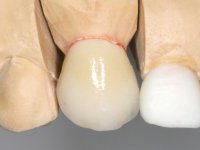

Treatment began with re-preparation of the cast post and core, with the purpose of placing the cervical finishing lines with an intra-sulcular location and simultaneously making a suitable temporary crown. With a very simple orthodontic treatment, the diastema was closed between the upper central incisors, and this position was stabilized with a wire placed on the palatal surface of the central, functioning as containment. Later, a slow orthodontic traction of tooth 2.2 was attempted, in order to reduce, although very slightly, the vertical bone loss in this area. At the end of the traction, tooth 2.2 was extracted and the area was provisionally rehabilitated with a composite resin crown bonded to the adjacent teeth. A dental implant was placed in the area of tooth 2.2 and the temporary crown was again bonded to resin, provisionally rehabilitating the patient during osseointegration. In tooth 1.3 a gingivectomy with an electric scalpel was performed, with the intention of raising the cervical level of 1.3 achieving greater harmony with tooth 2.3. Stabilized soft tissues were impressed using the open tray technique with putty and light addition silicones. Collection of the color of both the dental component and soft tissues was done by the ceramist in the office. In the laboratory, the impressions were transferred to plaster and gave origin to work models that were properly analyzed. It was decided to assemble a metal-ceramic abutment screwed onto the implant. This abutment was cast with a noble alloy and subsequently coated with coronary and gingival ceramics. Due to the inclination of the implant, the screwing inevitably conditioned the exit of the screw hole through the vestibular surface. In order to conceal this situation, the design of the abutment has already been conceived with the intention of accommodating on the vestibular surface the bonding of a feldspathic veneer. This abutment was tested in the mouth and adjustments were made in the gingival ceramic component. Its adaptation to the soft tissues was done in a subtractive way, with a drill, as well as additive, adding resin composed of gingival tonality.

This addition of resin would guide the ceramist in the final placement of the gingival tonality ceramic. The crown that would rehabilitate tooth 1.3 was cemented in this test session with glass ionomer cement, reinforced with composite resin. Once the laboratory work was finished on the veneer for tooth 1.2, the abutment, and the veneer for the implant, this was bonded in the mouth, after placement of the absolute insulation. The work completely satisfied the patient. For eight years, the patient had periodical check-ups, and was pleased with the treatment, but also began to show interest in an aesthetical intervention on the upper central incisors. Once the second phase of our intervention was decided, dental preparation of teeth 1.1 and 2.1 was performed for the placement of two feldspathic veneers. Particular care was taken in the distal inter-proximal preparation adjacent to the abutment of the implant.